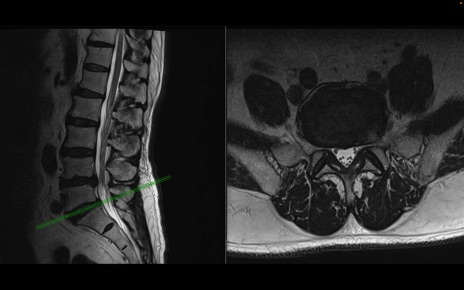

【整形】TIPS症例2 腰椎MRI 横断像と矢状断像

【症例】70歳代男性

【主訴】左下肢痛

【現病歴】2週間前くらいから腰痛、左下肢痛あり。左臀部から大腿、下腿外側のしびれが常時ある。歩行とともに同部位の痛みあり。

【身体所見】Lasegue70-/60+、Bragard-/±、PTR ±/±、ATR -/-、IP 5/5、TA 5/4、TS 5/5、EHL 右第1足趾なし/3、FHL 5/5、hypersthesia(-)、足背動脈触知良好

異常所見と診断は?